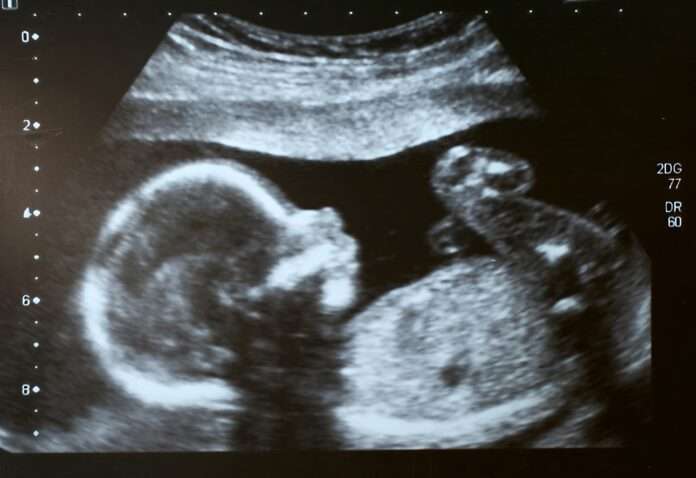

El seguimiento fue riguroso. Semanalmente, los médicos monitorearon la salud de la madre y el desarrollo del feto mediante ecografías. Tras el nacimiento, la bebé comenzó a recibir risdiplam oralmente a los ocho días de vida y continúa con el tratamiento hasta hoy, ya con dos años y medio. Es probable que lo necesite de por vida, pero los resultados son prometedores.